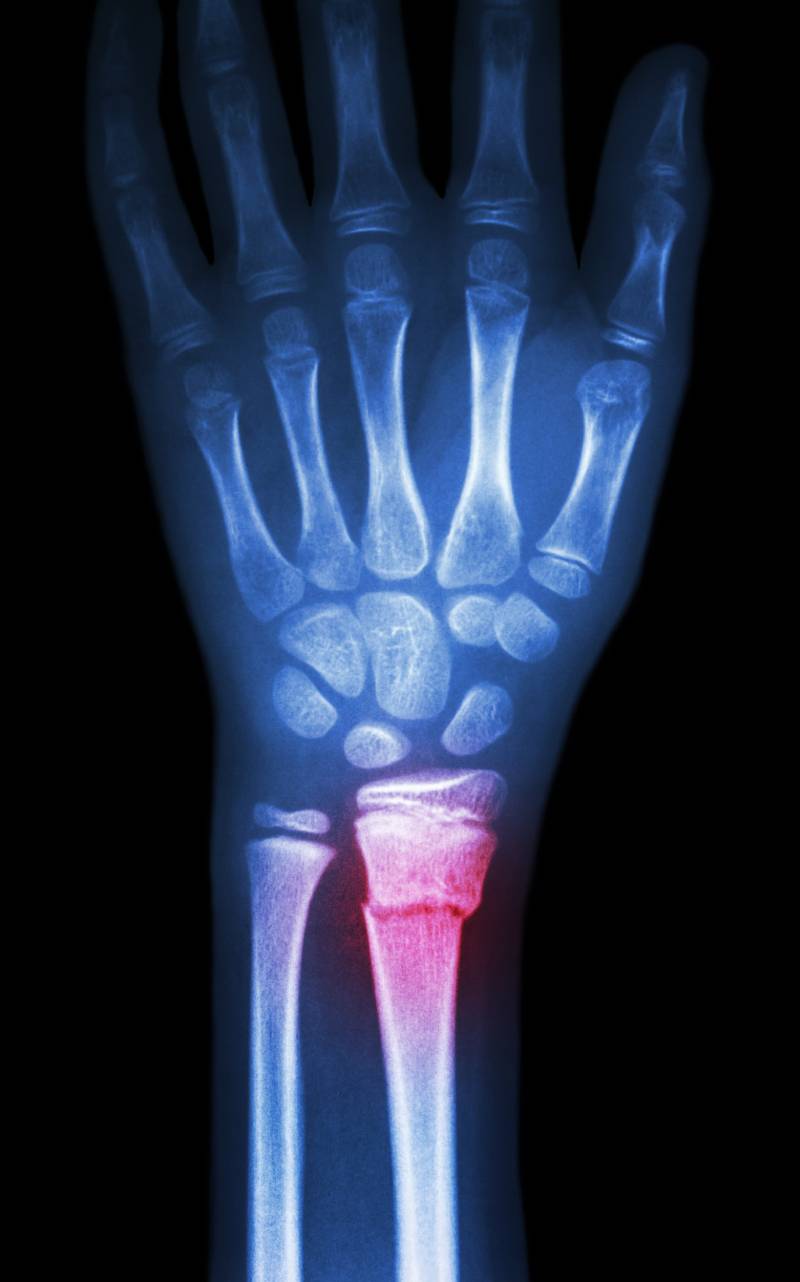

Radius Bone Surgery Recovery . In most cases, a patient who has undergone internal fixation surgery for a distal radius fracture may begin gentle wrist range of motion within 1 to 2 weeks of surgery, after which time a removable splint is. This article discusses the recovery process for both approaches, plus the pain management tactics that can be used for all patients. This leaflet was produced by the orthopaedic department, hull university teaching hospitals nhs trust and will be reviewed in may 2025. A distal radius fracture is one of the most common bone injuries. If you have not needed to contact us in the six weeks after your injury, you will be discharged and should seek advice from your gp. Because the kinds of distal radius fractures are so varied and the treatment options are so broad, recovery is different for everyone. Recovery time for a broken wrist depends on several factors, including the severity of your fracture and the method of treatment. Learn what to expect for treatment and recovery. Distal radius fractures can be reset either with surgery (open reduction) or without it (closed reduction).